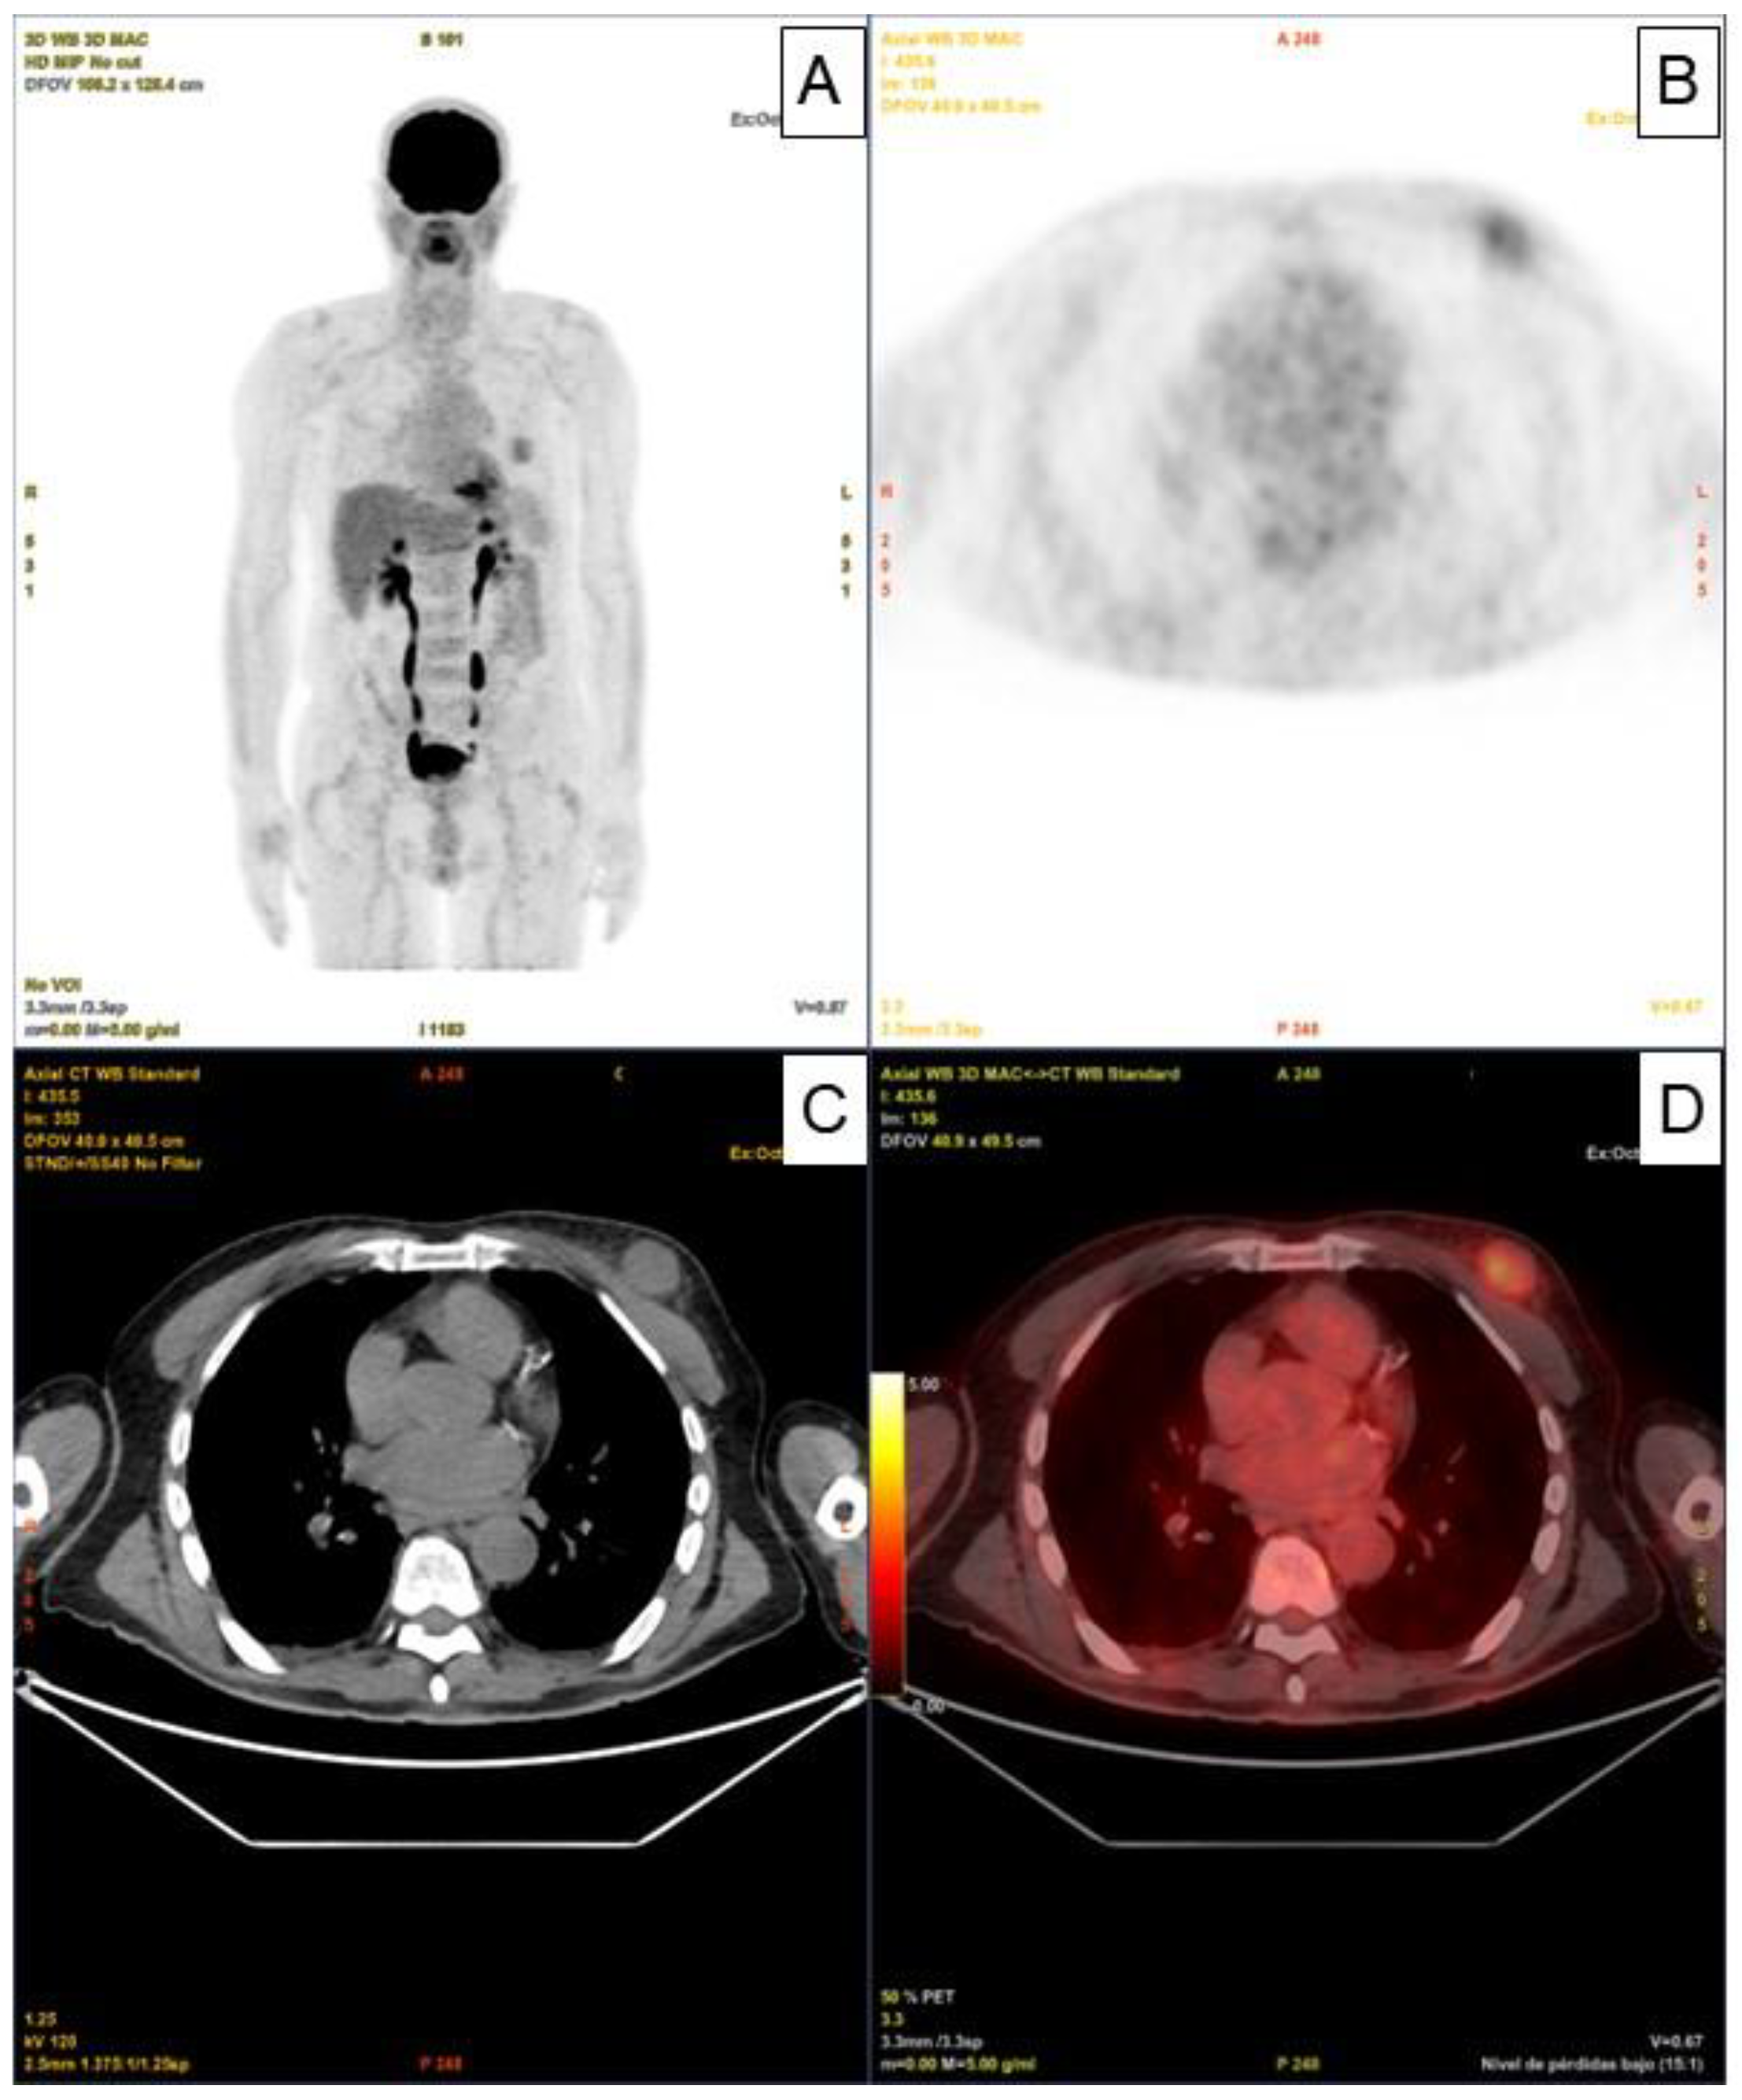

The An 80-year-old man with a history of Diffuse Large B-Cell Lymphoma (DLBCL) IV-BS stage and a high-risk International Prognostic Index (IPI) who was initially diagnosed and treated in another medical center. The patient underwent six doses of systemic treatment with the R-CHOP regimen. Once the treatment had finished, no adenomegaly or visceromegaly were found on physical examination. The patient had not reported fever or night sweats, and he gained weight during the last months (no B symptoms).The patient underwent 18F - Fluorodeoxyglucose (18F-FDG) positron emission tomography with computed tomography (PET - CT) scan for post therapeutic evaluation purposes, which evidenced partial response with decreased uptake and size in the lymph nodes, however, paradoxically, a nodular solid lesion with faint increase metabolic standardized uptake value (SUVmax) of 3 was detected in the upper outer quadrant of his left breast (Figure 1. Panels A, B, C, D).

Figure 1. (Panels A, B, C, D) 18F-Fluorodeoxyglucose (18F-FDG) positron emission tomography with computed tomography (PET-CT) showing a nodular solid lesion with a faintly increase metabolic standardized uptake value (SUVmax) of 3 located in the upper outer quadrant of his left breast.